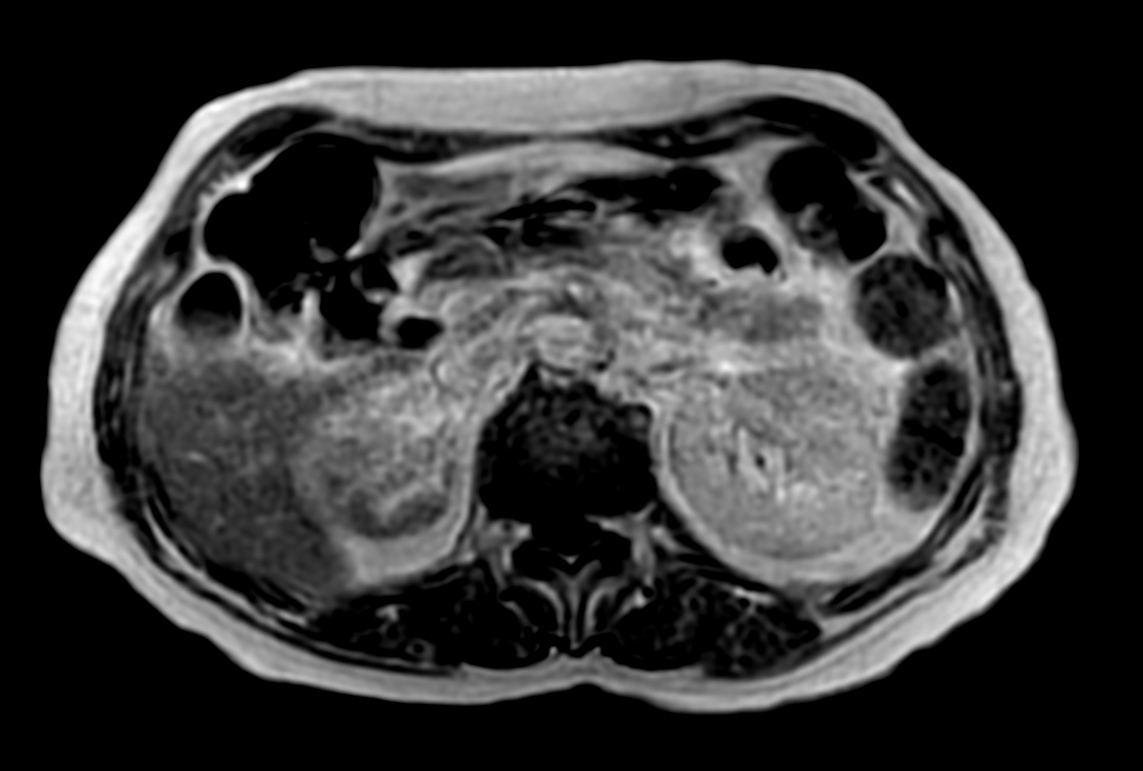

Patient with a kidney lesion. The ExamCard includes techniques for 3D imaging (PelvisVIEW, eTHRIVE) allowing for multiple image directions in one single scan, efficient fat-free imaging over large field-of-views (mDIXON XD), a multi-phase contrast-enhanced sequence (4D FreeBreathing) to improve imaging confidence and Compressed SENSE to accelerate the entire exam.

T2w TSE heavy weighted